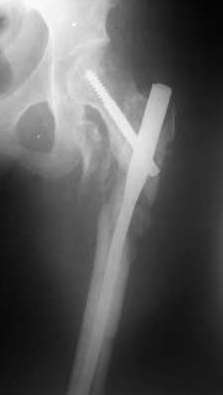

Девушка 21 года 02.10.07 г. пострадала в результате падения с высоты 4-го этажа при пожаре в одном из студенческих общежитий г. Москвы. Получила тяжелую сочетанную травму, в том числе закрытый оскольчатый чрез- и подвертельный перелом левой бедренной кости. Лечилась в одной из больниц столицы. Бедро было фиксировано при помощи скелетного вытяжения. Через полтора месяца после травмы переведена в институт им. Склифосовского. У больной имелись: поддиафрагмальный абсцесс, трахеопищеводный свищ, трахеостома, гастростома, несостоятельность швов раны передней брюшной стенки, укорочение левого бедра на 10 см (рентгенограммы при поступлении - рис 1.). В середине декабря был наложен спицестержневой аппарат, с помощью которого к сегодняшнему удалось устранить укорочение бедра (рис. 2). В течение последних 4-х дней устраняем смещение дистального отломка бедренной кости по ширине. Раны на передней брюшной стенке почти зажили. Температура тела и лабораторные показатели нормальные. Планируем выполнить закрытый остеосинтез левой бедренной кости удлиненным проксимальным бедренным штифтом производства фирмы "Остеомед". Нас смущает, что малый вертел бедренной кости остается значительно смещенным проксимально и кнутри.

Мы закончили репозицию отломков бедренной кости в аппарате (рис. 1, 2) у нашей пациентки и на прошлой неделе сделали ей вторую операцию. Штифт удалось ввести закрыто. Верхний шеечный винт держался очень плохо, поэтому мы его убрали и решили не ставить. Нижний держал очень плотно. Рентгенограммы после операции прилагаю (рис. 3,4). Пока не получилось сделать нормальный аксиальный снимок (больная с трудом сгибает и отводит ногу в тазобедренном суставе). Пока сделали боковую проекцию в положении на здоровом боку со сгибанием здоровой ноги.